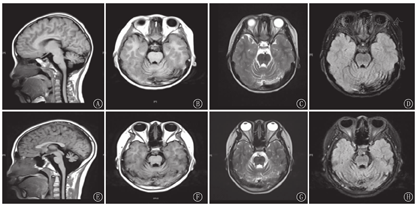

血尿便常规、血生化、甲状腺功能、脑脊液、胸片、心电图、肝胆胰脾+双肾上腺B超、染色体核型、尿有机酸分析及血氨基酸、肉碱和琥珀酰丙酮检验均无异常。雌二醇、孕酮、睾酮、催乳素、促卵泡生成素、促黄体生成激素均正常;血清极长链脂肪酸(VLCFA)正常。肌电图:多发性周围神经源性损害肌电改变(主要累及感觉、运动神经脱髓鞘)。听觉诱发电位:重度双侧感音神经性听力损失;先证者脑电图:异常儿童脑电图(背景活动减慢);其姐脑电图:正常青少年脑电图;先证者8岁头颅MRI:小脑脑沟宽深。其姐14岁头颅MRI:双侧小脑半球萎缩(图1)。先证者左腕关节正位片(骨龄片)正常。其姐14岁骨龄片:8枚腕骨发育,相当于10~11岁(图2)。先证者双肾B超正常;其姐双肾B超:双肾形态略小(左肾88 mm×39 mm,右肾85 mm×36 mm)。其姐14岁子宫附件B超:子宫形态小,宫体长经20 mm,前后径7 mm,横经10 mm,双侧卵巢显示不清(图3)。

DBPD是一种罕见的过氧化物酶体单个酶缺陷遗传病[2]。1989年由Watkins等[15]首次描述;1997年明确HSD17B4为其致病基因[16] 。本病以新生儿脑病、多发性神经病、精神运动发育障碍、双侧感音神经性听力损失、肝大、多发畸形为临床特征。目前还发现其他的临床表型,如卵巢功能障碍、小脑功能障碍、运动退化、骨成熟延迟、骨骼畸形等[1,3,4,6,7,8,9,11,17]。本组2例患儿为同胞姐弟,相同表型为新生儿癫痫发作、肌无力、精神运动发育迟缓、共济失调、足部畸形;姐姐还合并卵巢功能障碍、骨骼发育异常。临床电生理表现为双侧感音神经性听力损失、多发性周围神经病变。颅脑MRI示小脑萎缩,符合DBPD的诊断。患儿血清VLCFA正常,推测原因为酶活性残留。2例患儿严重程度有差异,推测原因为存在不同的酶活性残留量。

迄今,国外学者报道了100多例HSD17B4突变所致的DBPD病例;鉴定了数十种HSD17B4突变[1,10]。国内尚未见相关报道。本研究通过全外显子组检测,发现HSD17B4复合杂合突变,突变位点为c.686-2A>T和c.1171G>C,分别来自父母双方,符合常染色体隐性遗传规律,美国医学遗传学和基因组学学会指南[18,19]评级为致病性变异。HSD17B4突变导致过氧化物酶体脂肪酸β氧化的破坏是其主要发病机制;β氧化底物VLCFA的累积是DBPD最重要的特征之一[1,2]。当酶活性残留,VLCFA正常时,脑白质和小脑白质脑病、脑皮质发育异常等"过氧化物酶体模式"可作为DBPD的诊断线索[20,21]。HSD17B4突变的病例回顾性研究显示,VLCFA正常时,部分病例可仅见小脑萎缩,以双侧感音神经性听力损失和女性独有的性腺发育不良为典型临床特征[7,11]。这些特征支持本组2例患儿诊断DBPD。